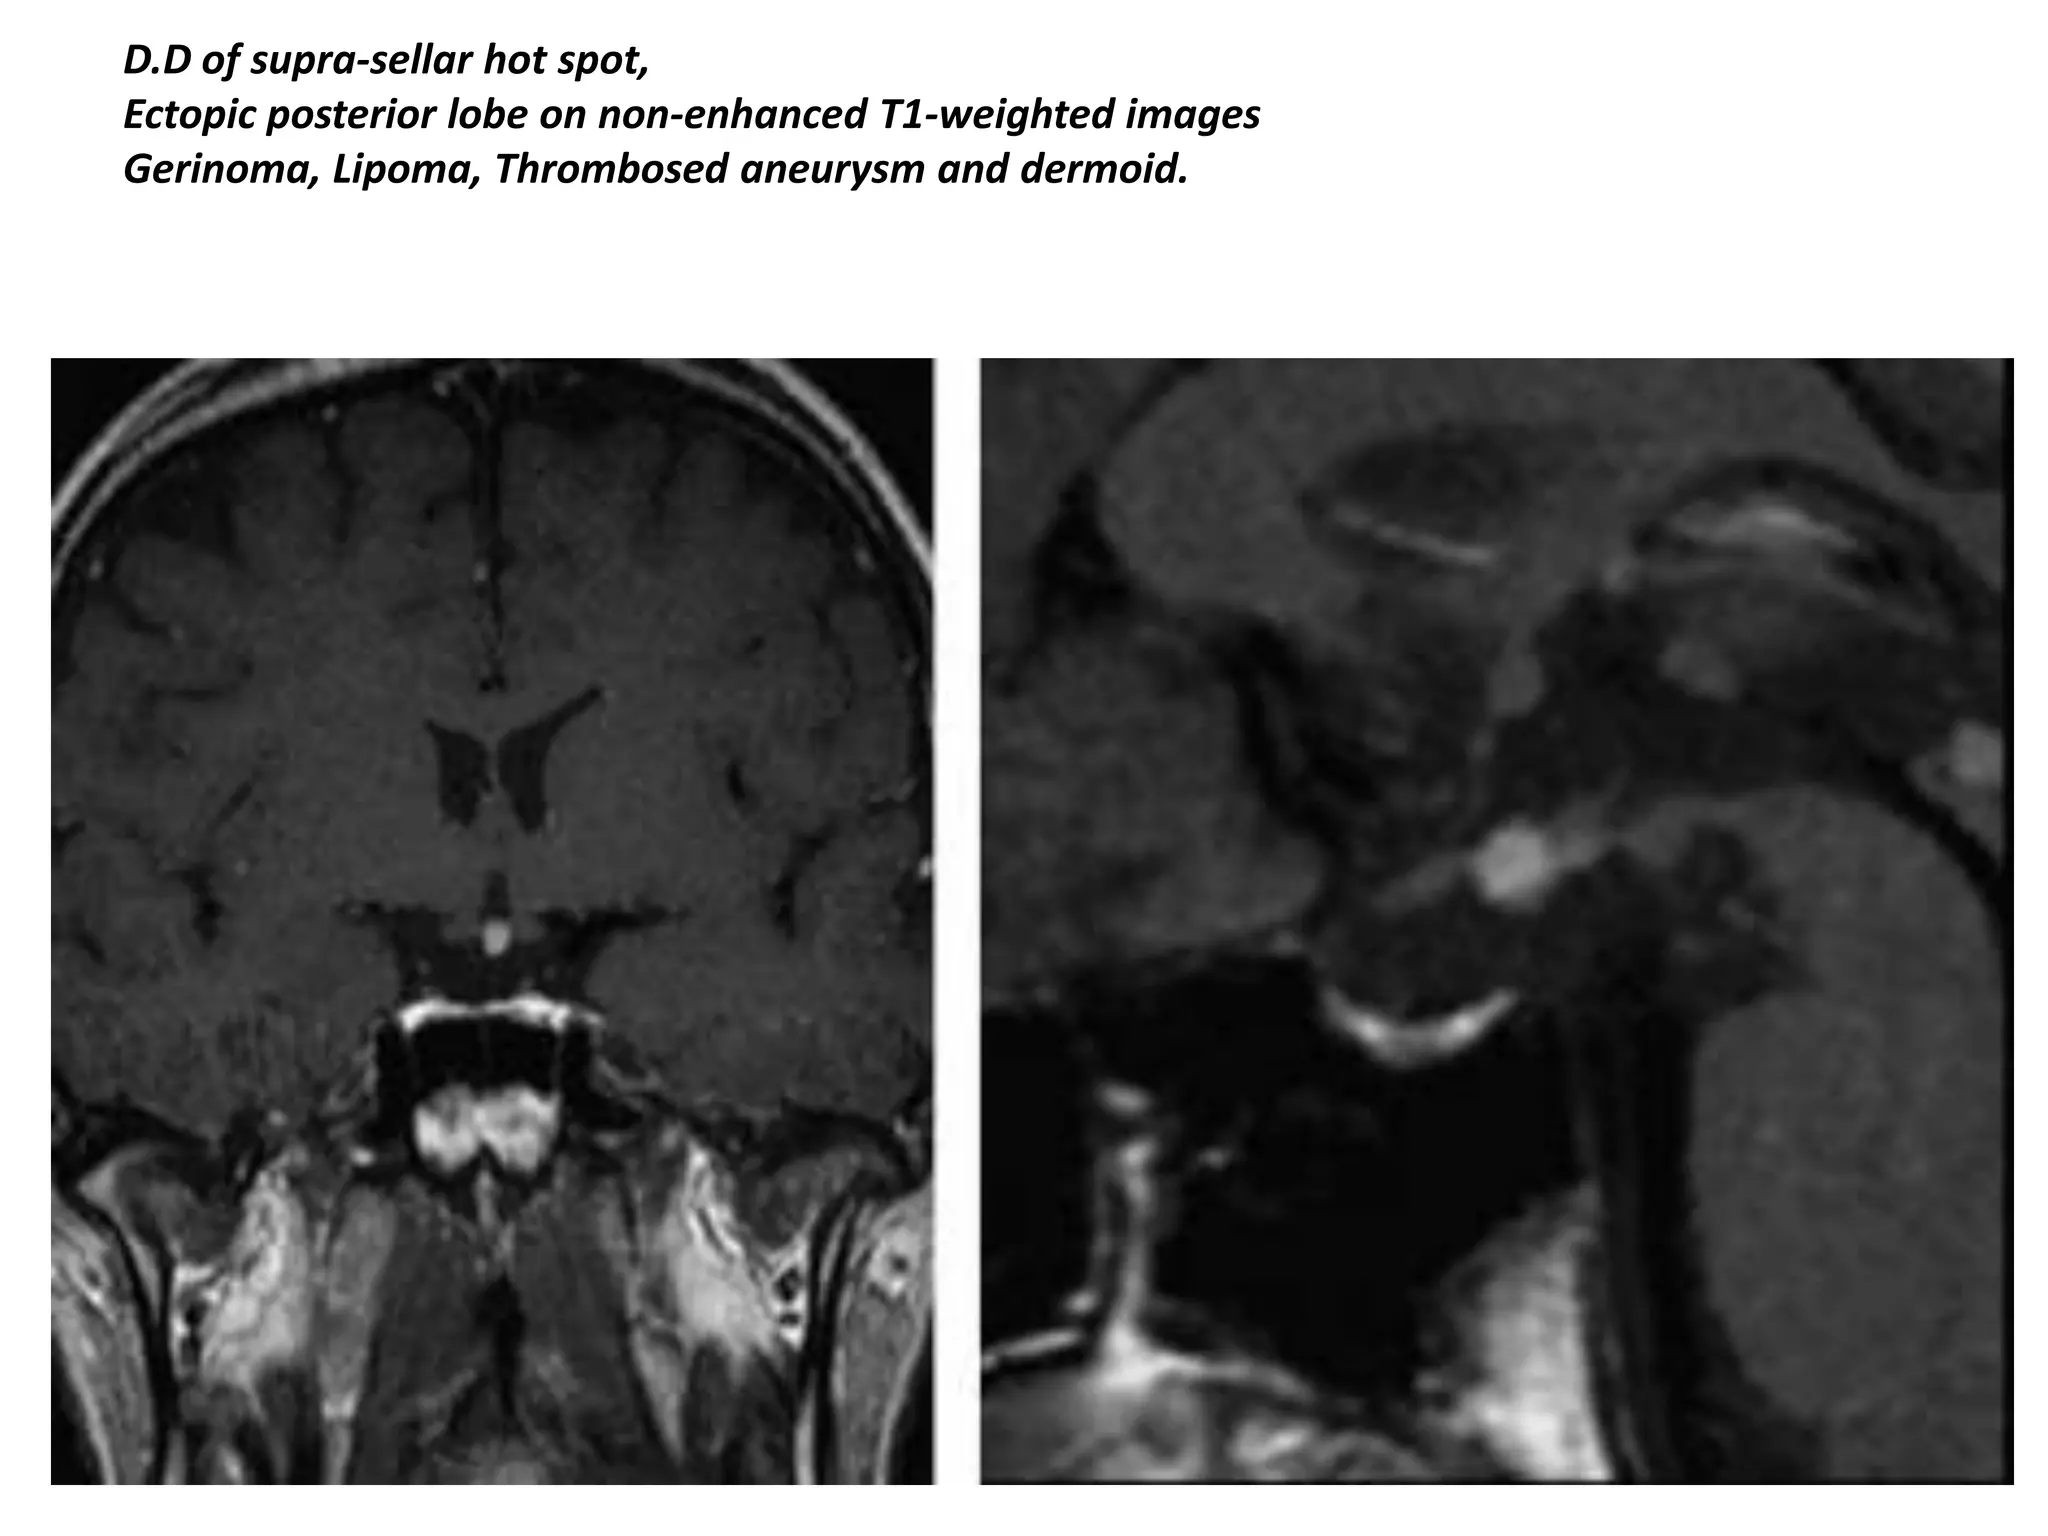

D.D of supra-sellar hot spot,

Ectopic posterior lobe on non-enhanced T1-weighted images

Gerinoma, Lipoma, Thrombosed aneurysm and dermoid.

D.D of supra-sellarhot spot, Ectopic posterior lobe on non-enhanced T1-weighted images Gerinoma, Lipoma, Thrombosed aneurysm and dermoid.